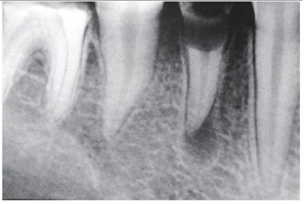

“A cárie e a infecção do sistema de canais

radiculares representam as principais fontes de

agressão microbiana persistente à polpa e aos

tecidos perirradiculares.”